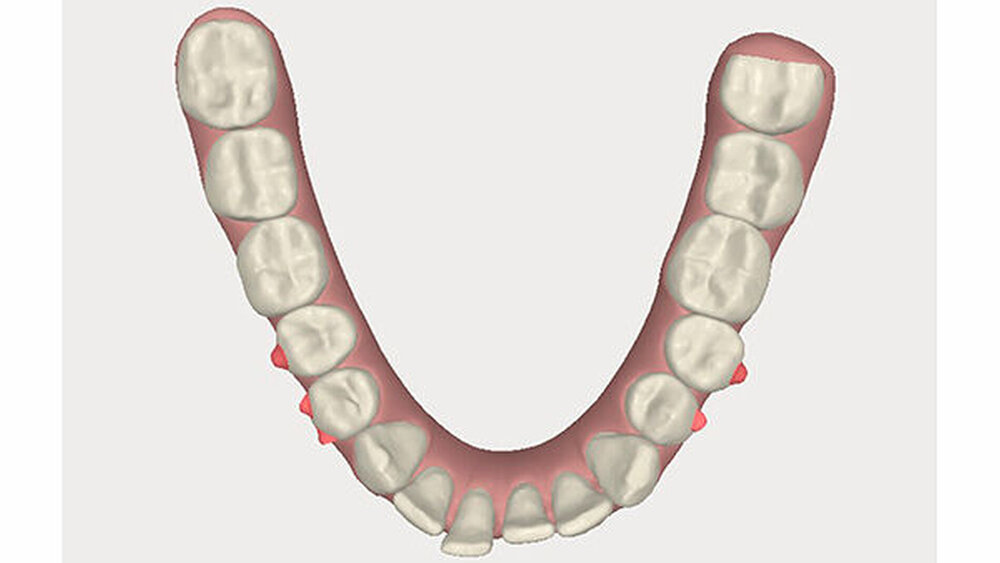

Um einen kompletten Lückenschluss im Oberkiefer zu ermöglichen, musste im Unterkieferfrontzahnbereich zusätzlich zur Derotation und Positionierung der Zähne - insbesondere Zahn 41 - von approximaler Schmelzreduktion, kurz ASR , Gebrauch gemacht werden, um einer Tonn`schen Diskrepanz entgegenzuwirken (Abbildung 4).

Nach Ausgliederung der insgesamt 14 Invisalignschienen, die der Patient jeweils drei Wochen getragen hatte, wurden ihm sowohl im Unter- als auch im Oberkiefer Sechs-Punkt-Retainer eingegliedert, um eine Schienung und Stabilisierung der Zähne untereinander zu ermöglichen. Zusätzlich wurden für die Nacht Retentionsschienen gefertigt.